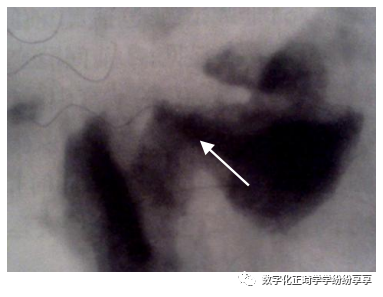

髁突小凹陷缺损

曲面断层片怎么看正畸【曲面断层片(全景片)】如何解读和查看:牙周?牙体?牙髓?关节?_https://www.jmylbn.com_新闻资讯_第29张

髁突经咽侧位片示髁突前斜面骨质呈小的凹陷状缺损,周围骨质密度减低

髁突前斜面广泛破坏

曲面断层片怎么看正畸【曲面断层片(全景片)】如何解读和查看:牙周?牙体?牙髓?关节?_https://www.jmylbn.com_新闻资讯_第30张

髁突经咽侧位片示髁突前斜面密质骨边缘消失,表面不整齐,有较广泛的骨质侵蚀及破坏